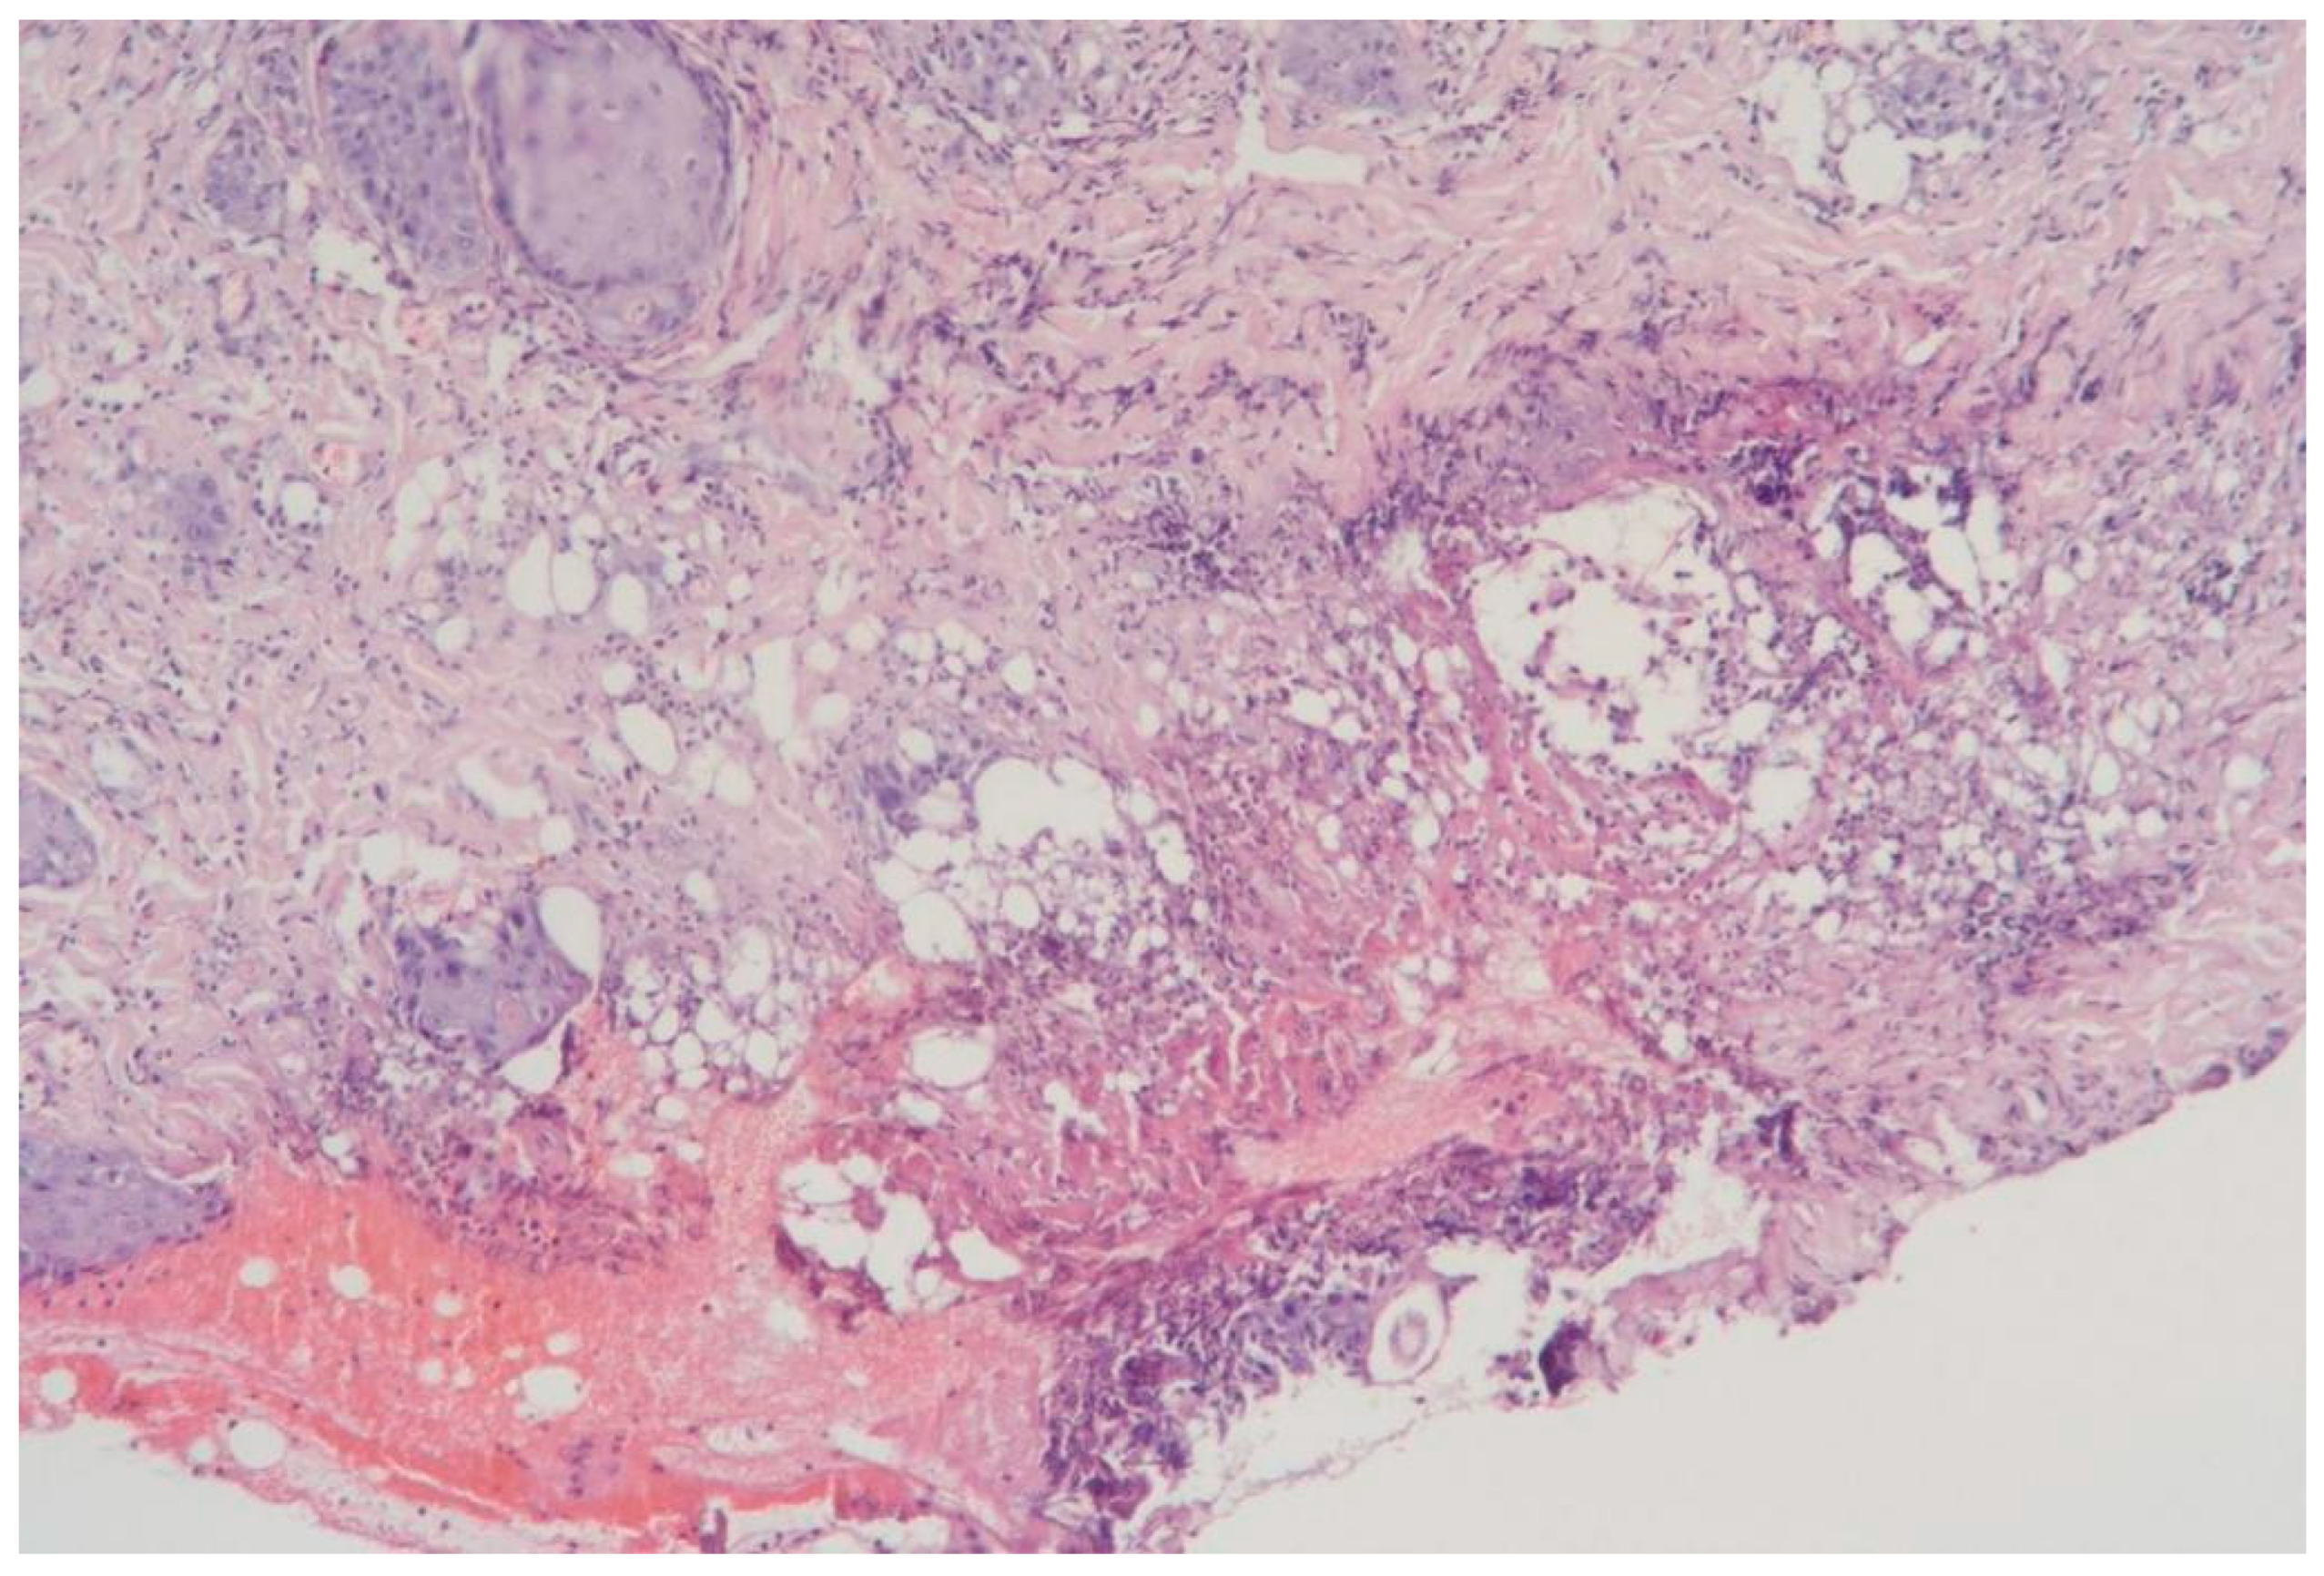

3.1.10. Clinical Case 10: Adipose Tissue Dissection Area, 25 W (See Figure 11)

Description: Coagulative necrosis mainly spread along the septa. The adipose tissue was preserved, but extensive hemorrhages were observed in the interlobular spaces. Inflammatory changes were absent. The vessels were dilated and markedly congested, with thickened and edematous walls.

Figure 11. Changes in subcutaneous adipose tissue following exposure to the thulium laser at 25 W. H&E staining, 10× objective magnification.

Thus, when exposed to the thulium laser at 20 W, the surrounding tissues exhibited the least pronounced necrotic changes, with no hemorrhages or inflammatory alterations.